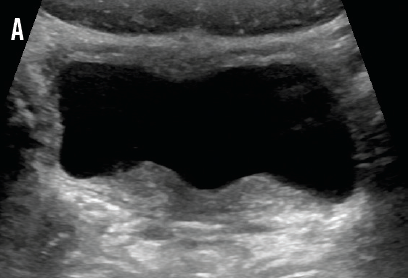

IgA and C4 values were normal, and the C3 value was slightly elevated, which decreased the likelihood of IgA nephropathy, PSGN, and lupus nephritis. Normal kidney function made ATN less likely. A normal IgA level and a lack of skin or joint manifestations ruled out HSP. Urine and stool bacterial cultures returned negative. Renal ultrasonography demonstrated normal kidneys with minimal bladder wall thickening (A and B) and an incidental finding of uterus didelphys. The patient continued to pass clots in her urine, prompting further investigation for viral hemorrhagic cystitis. Urine polymerase chain reaction (PCR) test results were negative for BK virus, but PCR results for urine and serum adenovirus returned positive on hospital day 3.